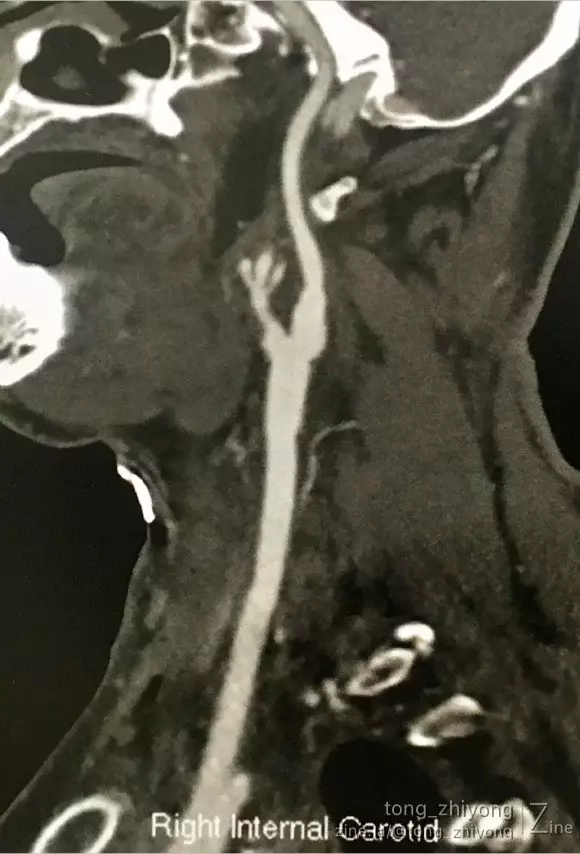

术后一周CTA可见:颈动脉通畅,颈内动脉起始部管径适度增宽。